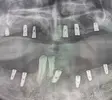

Implant Treatment